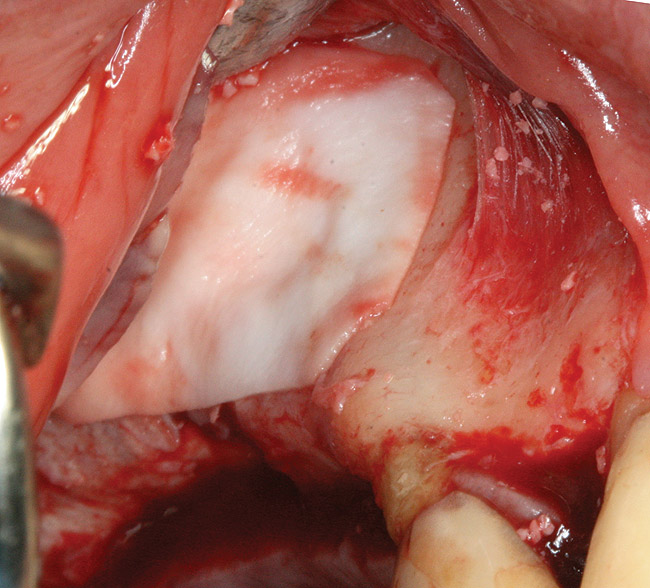

Fig 3. Schneiderian membrane from the sinus walls is elevated.

Figure 3

The technique described below is based on a deep buccal full-thickness flap with vertical release in the canine area, followed by creation of a “window” at the lateral wall of the sinus (Figure 2). The bony window is either removed or rotated medially with the sinus membrane and pushed inward. The Schneiderian membrane is then separated from the bone anteriorly, posteriorly, and medially until clinically sufficient space is established (Figure 3). The created space, which occupies the lower third of the sinus, is filled with a bone graft (Figure 4), and the lateral access window is covered with a collagen membrane (Figure 5).